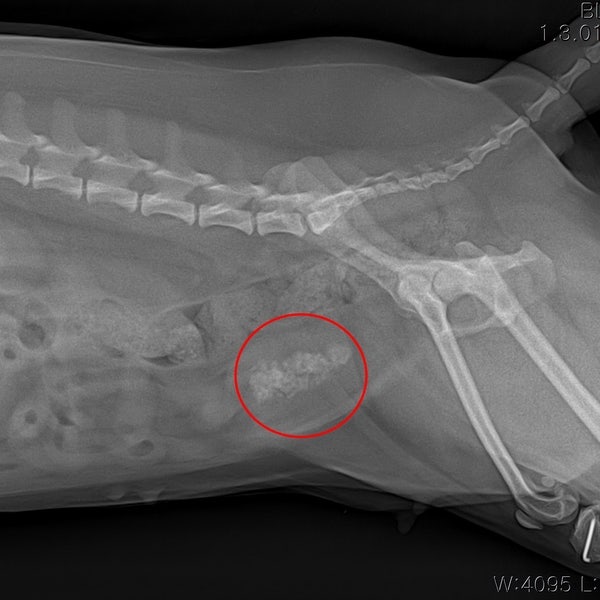

강아지 누렁이가 몇 번 피 묻은 소변을 본 것 외에 아파하지는 않으니(결석도 작고 다수) 그래서 우선 약 처방을 받고(이게 항생제 같은 건가?) #결석사료를 사서 수술은 마지막 보류로 남기고 그 전에 자연치유 관리에 들어가기로 했다.

#개의 방광결석증상 보통 이 증상이 소변을 거의 볼때쯤 위와 같이 피가 섞여 나온다; (이번에는 좀 진해서 놀랐다;;)

소변이 나오고 안의 결석이 방광벽을 긁기 때문이라고 들었다. 사람들도 결석때문에 기절할정도로 아프다고 한사람도 있다던데;;

우선 결석이 크지 않고 관찰하면서 요도를 막지 않는 이상 되도록 물 마시는 양을 늘려 배변 횟수를 늘려 소변으로 배출시켜 보자는 게 우선적인 내 선택이다.